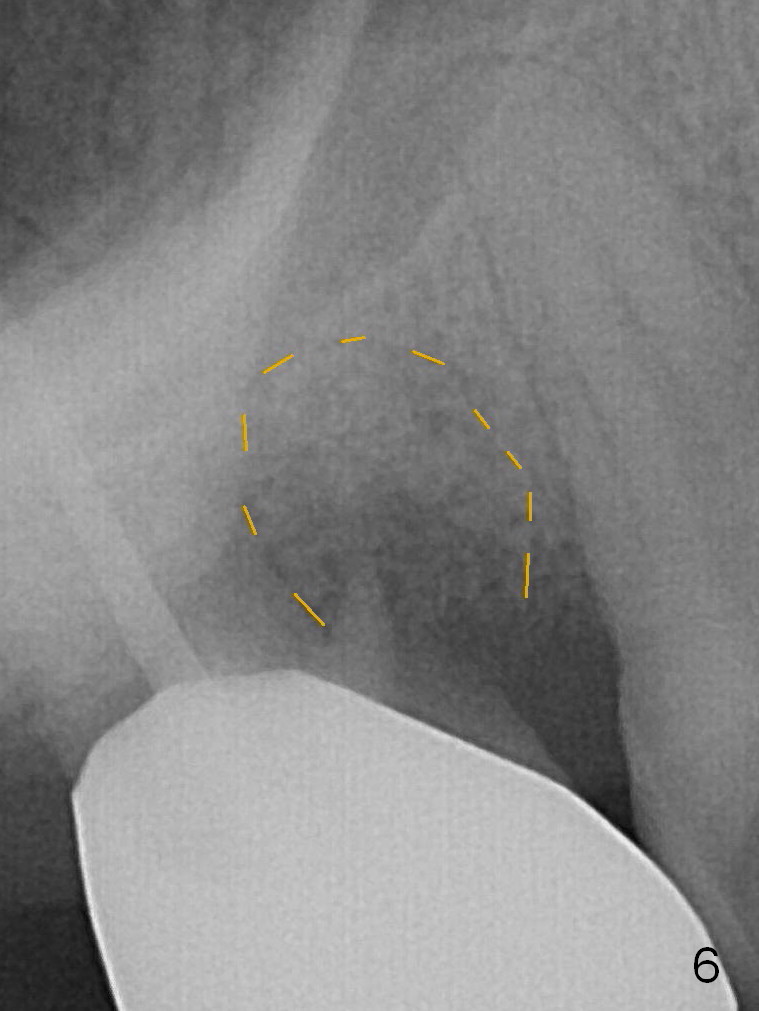

A 56-year-old man has discomfort associated with the tooth #3 one year and a half after root canal therapy (Fig.1: mesiobuccal root vertical fracture). Since an implant is just placed at #19 and another one will be encouraged to be placed at #2 (Fig.2), root amputation may be a valid treatment modality (Fig.3,4). After debridement and Clindamycin topical application, allograft/Osteogen is placed (Fig.5,6 (dashed line)), followed by Osteogen plug (Fig.7 *). Discomfort apparently shifts to the distobuccal root 9 months postop, while the MB defect seems to heal (Fig.8 *). Extraction and implant is expected.